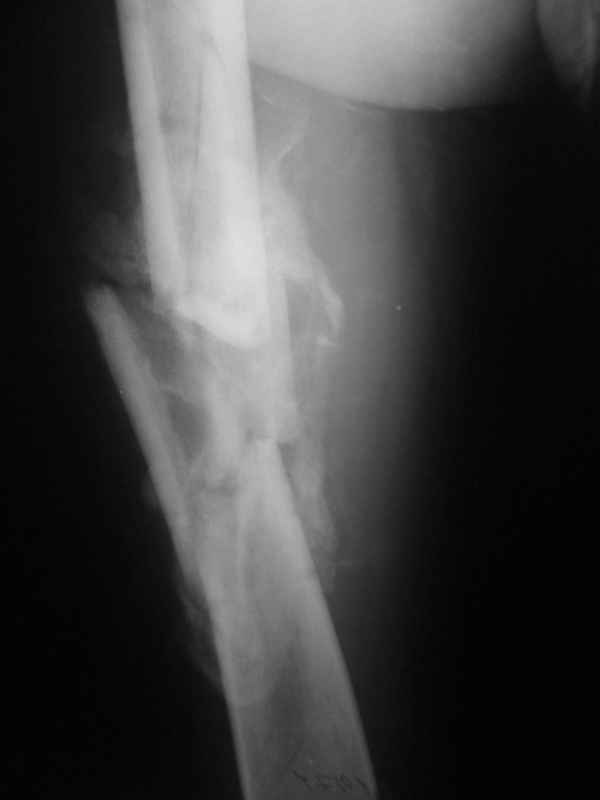

[Ortho] Неправильно срастающийся оскольчатый перелом бедра

Вложение не в текстовом формате было извлечено…

Имя     : 004.jpg

Тип     : image/jpeg

Размер  : 15053 байтов

Url     : http://weborto.net:8080/pipermail/ortho/attachments/20110406/c06e2959/attachment-0007.jpg